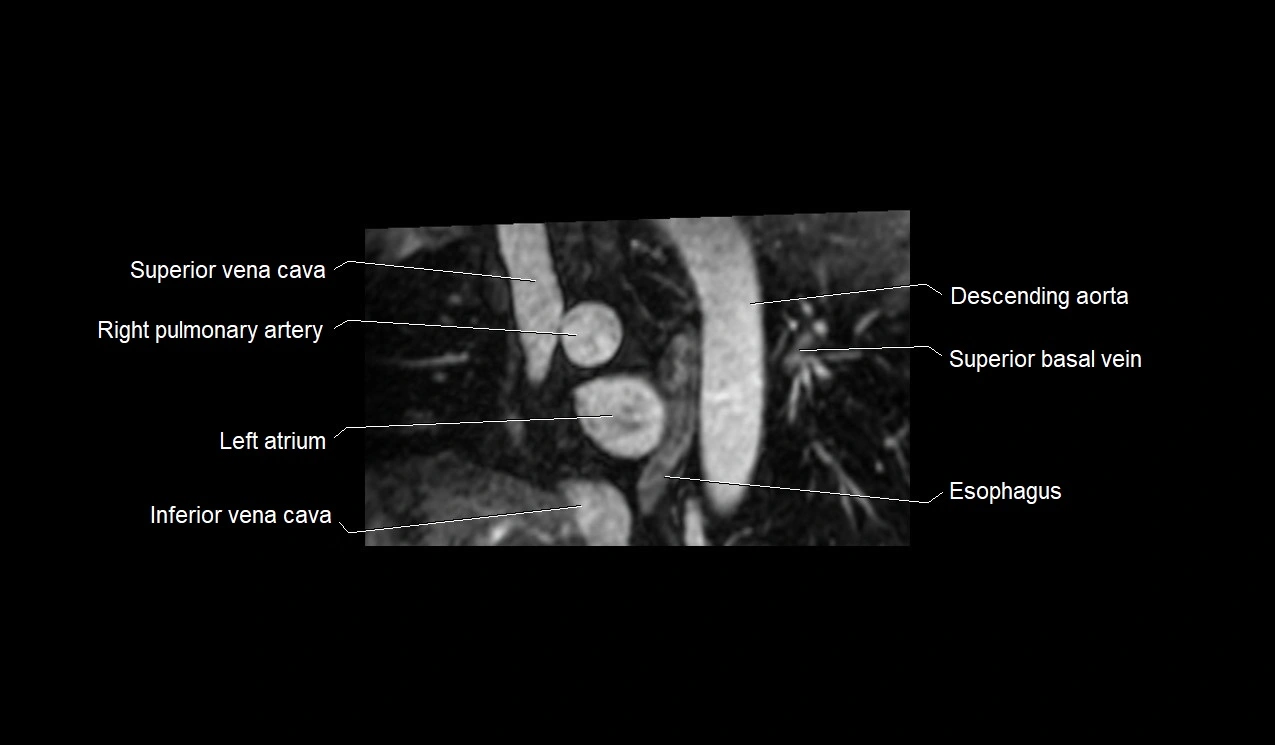

- Superior vena cava

- Right pulmonary artery

- Left atrium

- Inferior vena cava